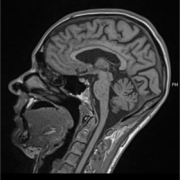

Diese Woche war ich mal wieder im MRT. Ein Termin, der jedes Jahr ansteht. Ein Termin, der rational „Routine“ ist – und emotional alles andere als das. Dramatisch gesagt, fühlt sich jedes MRT an, wie ein Blick in die eigene Zukunft. Man hofft, dass es ruhig geblieben ist. Man fürchtet, dass etwas Neues aufleuchtet. Diesmal: […]